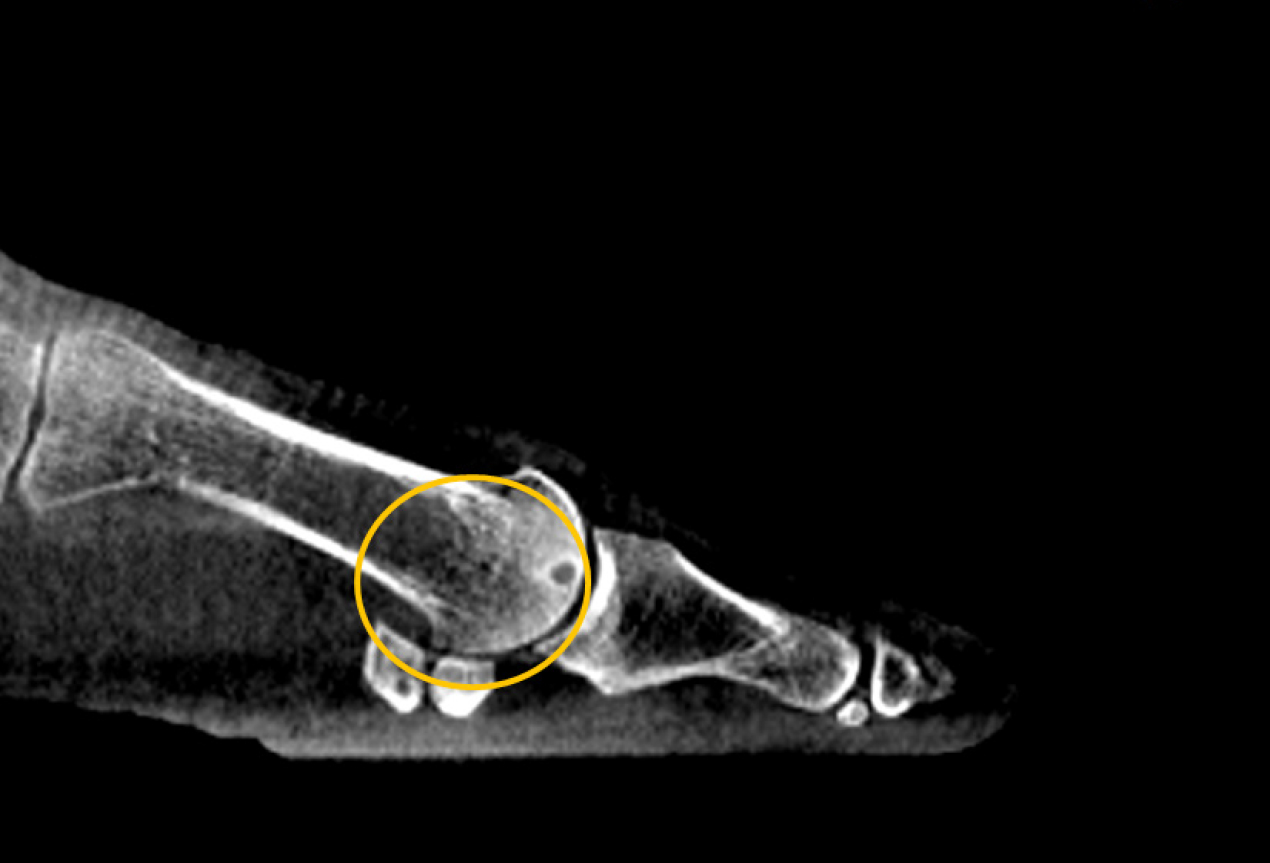

- Diagnostics of complex and avulsion fractures

- Diagnostics of tear of the tibiofibular syndesmosis

- Diagnostics of subluxations in the talonavicular joint and other foot joints in patients with complex post-traumatic deformities, the diabetic foot, and the Charcot’s foot

- Maximally accurate post-operative osteosynthesis control

- Maximum efficiency of surgical interventions due to ATRISS state-of-the-art tools for planning osteosynthesis